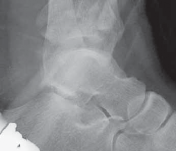

TECH FIG 2 • A–C. Imaging of 43-C3 pilon fracture with mostly anterolateral injury pathology. D. Anterolateral approach. This is a modification of Bohler’s incision, in line with the fourth metatarsal and extending proximally between the tibia and fibula. ### TECHNIQUES